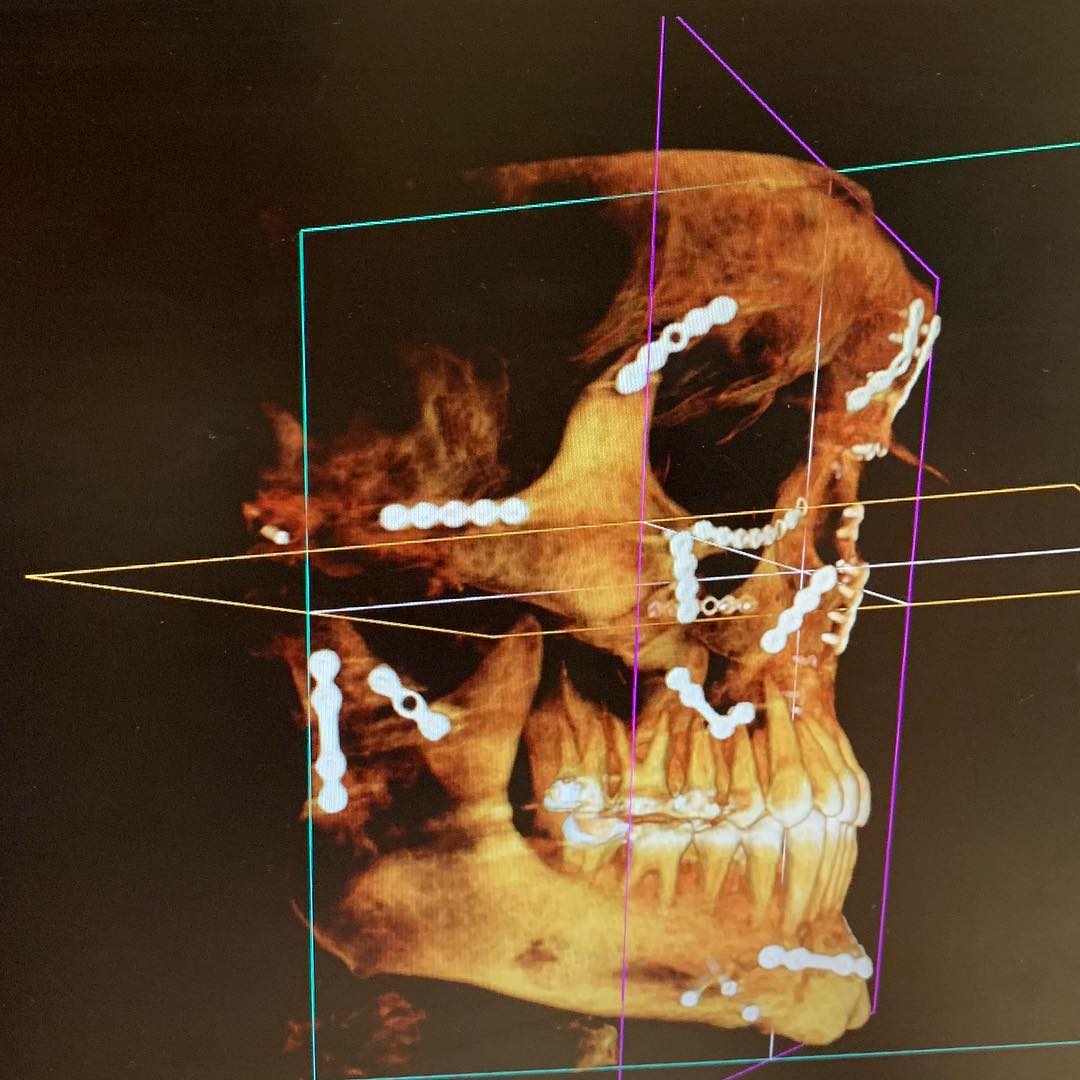

Weston Peick mostra a reconstrução do seu rosto

Weston Peick mostrou o quanto de trabalho foi necessário para reconstruir seu rosto após o acidente no Supercross de Paris, em novembro.

“21 placas quatro parafusos e um enxerto ósseo”, disse Peick sobre a cirurgia que ele teve que suportar após ser atropelado no primeiro main event da noite. Peick se recuperou bem, mas não foi divulgado se ele poderá voltar a competir.